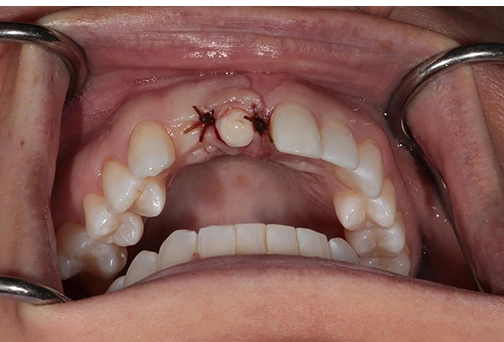

Appointment #4: Custom healing abutment placement appointment

The existing healing abutment was removed, and a lab-designed custom healing abutment was installed. It allowed us to shape the emergence profile and ensure the best gingival aesthetics.